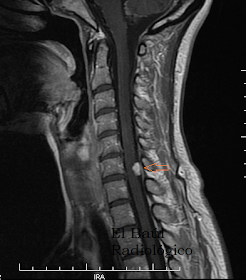

FIGURA 1-A) Imagen FSE- T1. La flecha señala una pequeña lesión hipointensa que impronta sobre la médula cervical. Schwannoma intradural extramedular.

FIGURA 1-B) Imagen FR-FSE-T2. En esta secuencia los schwannomas aparecen ligeramente hipointensos (oscuros) (Flecha).

FIGURA 1-C) Imagen FSE-T1 Gadolinio. El schwannoma se realza de forma intensa después de administrar contraste.